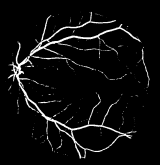

Segmentation of blood vessels in retinal images

Segmentation of blood vessels allows a noninvasive method to diagnose diseases such as diabetes, hypertension and cardiovascular diseases.